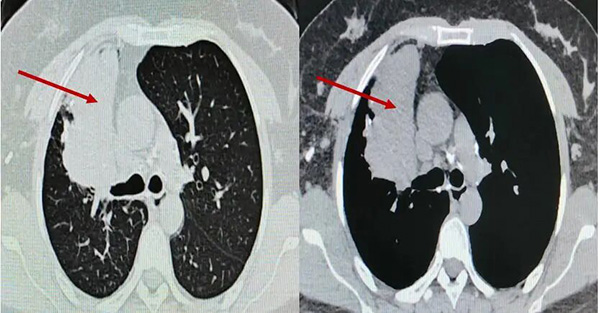

患者为36岁女性,既往有肺结核病史,近两年反复出现低热、咳嗽症状,胸部CT提示右肺上叶大片实变、坏死及多发黏液栓,气管镜显示支气管瘢痕性闭塞,化验提示曲霉菌感染。患者曾接受长期口服抗真菌药物治疗,但病灶未缩小,并出现视神经损害等药物并发症,停药后病情仍反复,右肺出现新发病灶。

▲术前胸部CT

入院后,呼吸与危重症医学科介入团队对患者病情进行全面评估。完善胸部增强CT提示:右肺上叶大片状实变并坏死,支气管完全闭塞。由于前期单纯口服抗真菌药物效果不佳,因此联合气管镜下介入治疗势在必行。经过认真评判,团队制定了详细的气管镜下介入诊疗计划。治疗过程包括:超声支气管镜引导下精准穿刺,高频电刀微创开窗建立引流通道;钳夹清除远端大量坏死组织;局部灌注抗真菌药物以提高病灶药物浓度;结合球囊扩张与超细冷冻冻融治疗,扩大引流窗口;并多次行镜下冲洗,彻底清除分泌物与坏死物。

经过系统治疗,患者低热症状消失,精神状态逐步好转。术后气管镜复查显示右上叶前段闭塞支气管已重新开放,坏死物基本清除;胸部CT显示原新发病灶消失,前段病灶引流通畅,炎症吸收良好,成功保留了右肺功能。